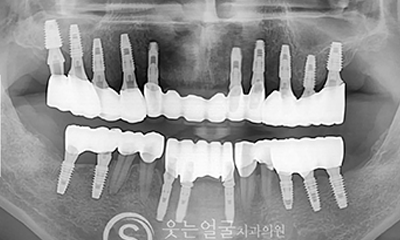

While the initial implant procedure is crucial, revision surgery may sometimes be necessary due to issues such as incorrect placement,infection, or bone loss.

SMILE FACE DENTAL CLINIC leverages extensive clinical experience and precise diagnostic equipment to accurately identify the causes of problems with existing implants and to perform safe, systematic revision procedures.

Implant

Before & After Photos